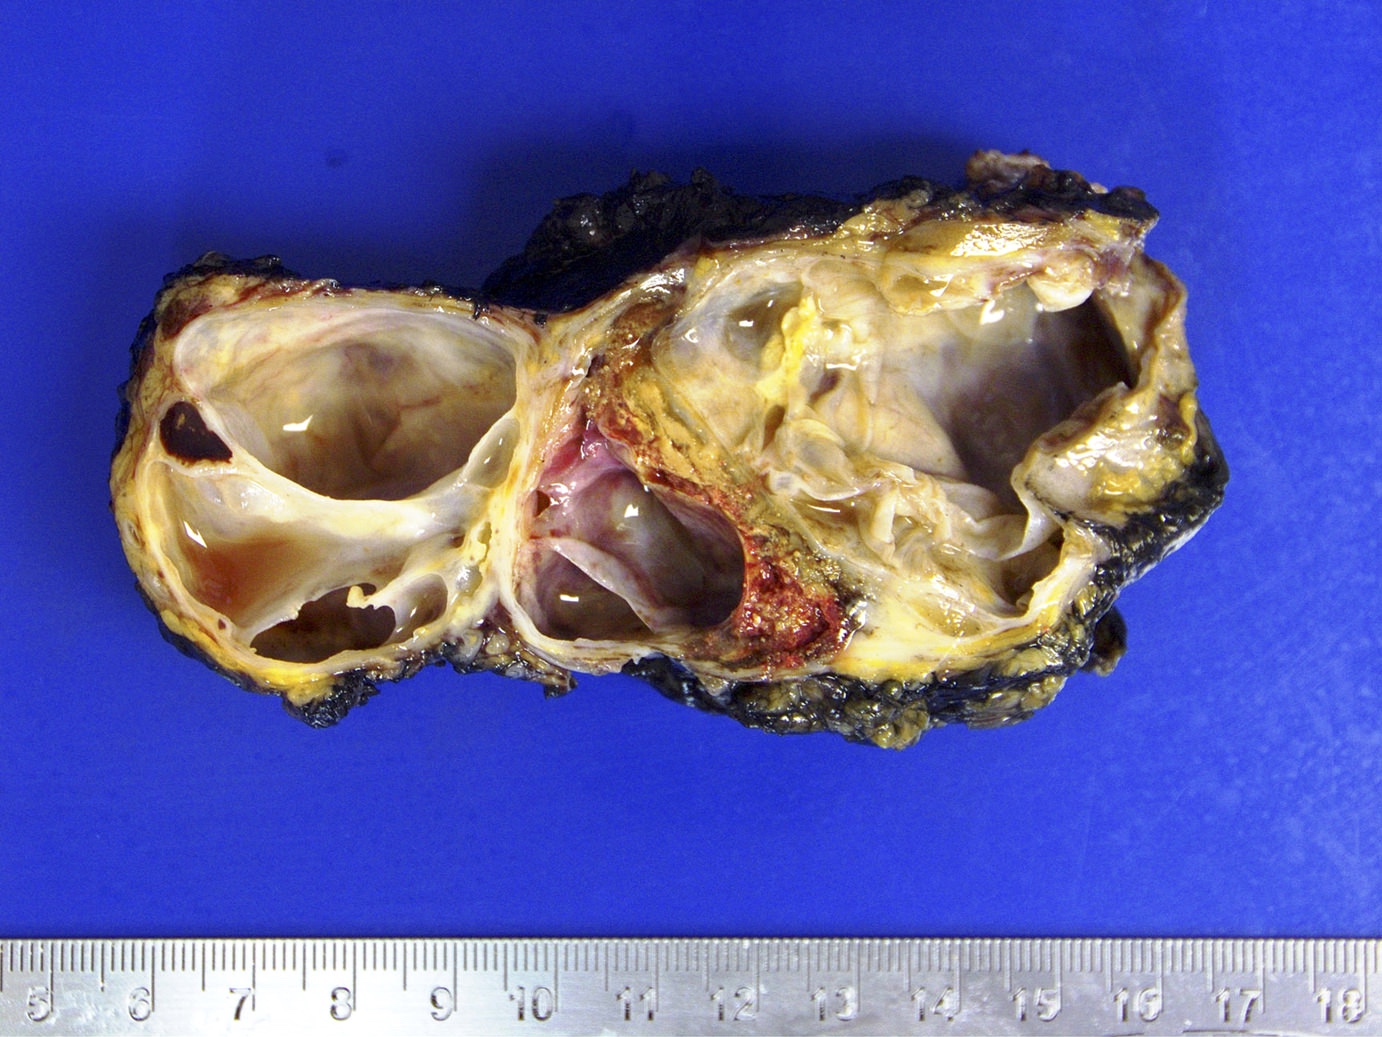

Gross images

Contributed by Debra L. Zynger, M.D.

Mixed germ cell tumor (pT2)

Seminoma (pT2)